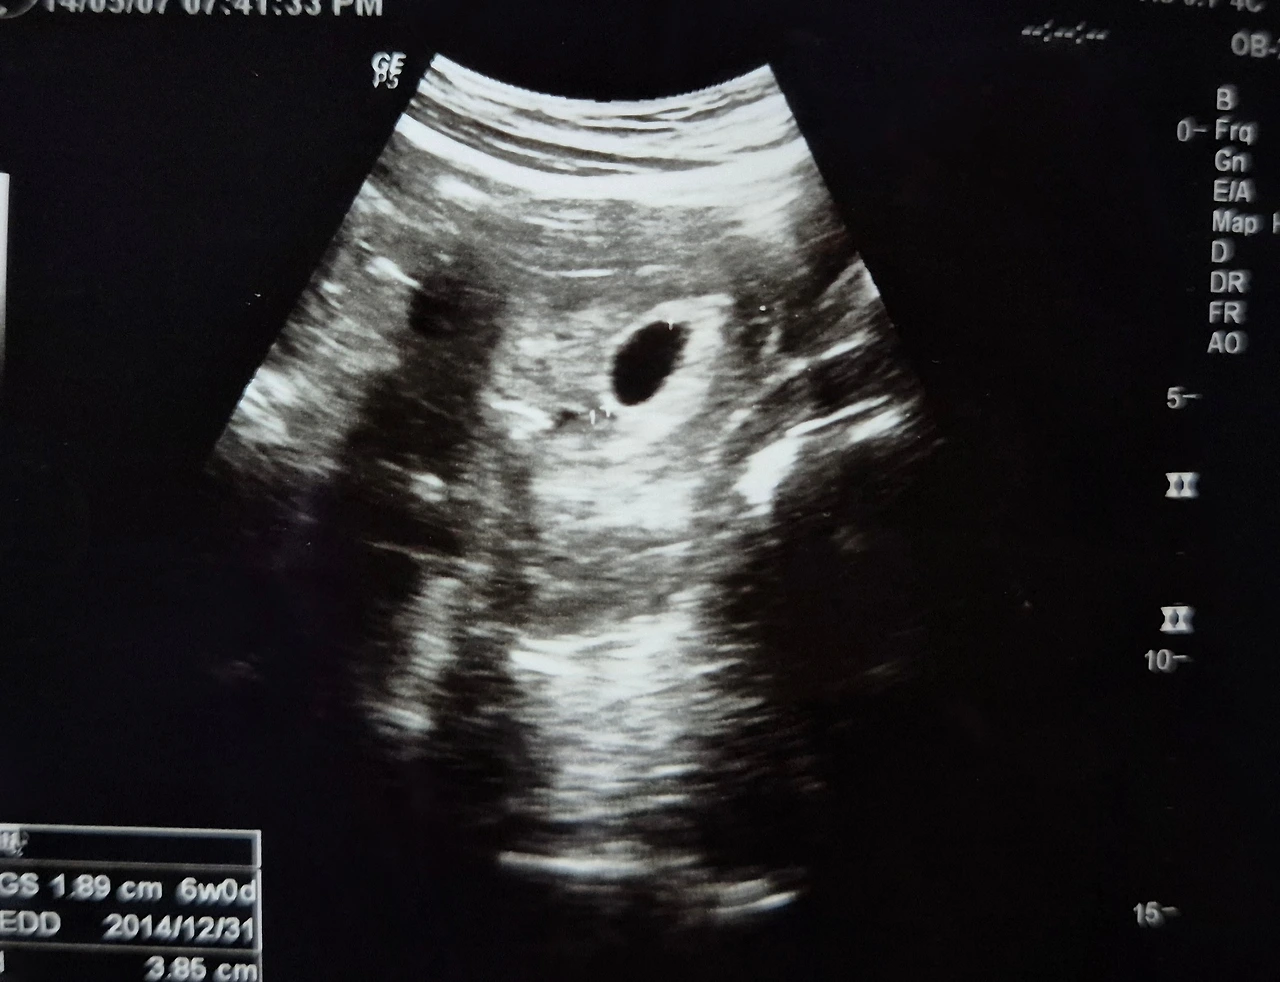

더 이상 몸이 보내는 신호를 외면할 수 없었다. 약국에서 임신 테스트기를 사고, 결과가 나오는 그 몇 초가 나에겐 영겁의 시간처럼 느껴졌다. 결과는 예상대로 두 줄, 임신이었다. 아이를 단번에 품게 되는 축복을 받았음에도, 그 순간 나는 또 한 번 미루어진 계획에 철없이 원망의 마음이 앞섰다.

호르몬 탓이었을까, 울음을 터뜨리며 남편에게 그간 하지 못했던 설움을 토로했다. 기다리고 기다려, 이제 겨우 우리도 둘만의 삶을 시작했는데. 데이트다운 데이트는 언제 해본 건지 기억도 안 나는데. 아직 신혼여행도 못 갔는데. 또 기다려야 한다니. 이렇게 나의 꿈의 신혼 생활도 끝이구나 생각하니, 억울하게 느껴져 목놓아 울고 말았다. 우는 와중에도 뱃속 아기가 내 말을 듣고 상처를 받을까 걱정도 잠시 스쳤다. 눈물을 머금고 비행기 티켓과 스냅사진을 취소했다. 수수료까지 물어야 한다는 이메일을 받으니 더 억울해서 남편 몰래 한 번 더 울었다. 그곳에서 사기로 했던 나의 첫 샤넬백도 함께 물 건너가는 순간이었다.

샤넬 대신 우리에게 온 너의 태명을 코코라고 지었다.